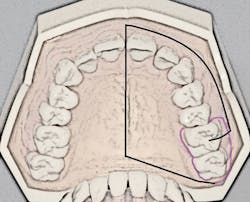

The porous palatal tissue and bone allow penetration of the anesthetic to the dental plexus of the ASA and MSA nerves (on one side), which provide innervation to pulps of the premolars through incisors and, sometimes, the mesiobuccal root of the first permanent molar. The same-side hard palate and palatal gingiva are also anesthesized (see Figure 1).

Recall that the posterior superior alveolar (PSA) nerve block, with its 95% success rate, anesthetizes the molar teeth and associated buccal soft tissues. The ability to anesthetize an entire maxillary quadrant (hemimaxilla) during NSPT with the AMSA and the user-friendly PSA block combination (see Figure 1) results in a reduction of the total number of injections (two versus four to five) and also a reduction of total volume of anesthetic (1.25 to two cartridges versus two to three cartridges). Patients appreciate the reduced number of penetrations as well as the lack of numbness of the lip and face.